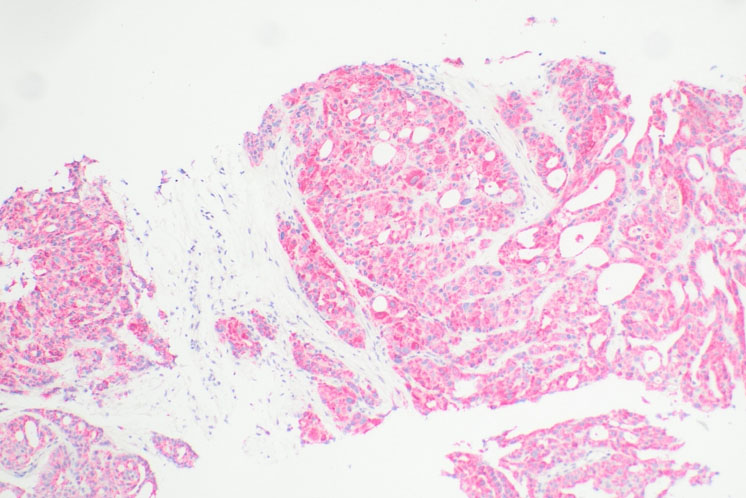

The patient was then referred to surgery for further work-up. A right breast ultrasound showed no breast abnormalities but found enlarged, suspicious right axillary lymph nodes. A subsequent positron emission tomography (PET) scan showed hypermetabolic right axillary lymph nodes and cutaneous fludeoxygluoce-18 uptake in the right axilla. Surgery proceeded with an ultrasound-guided percutaneous core needle biopsy of the largest enlarged lymph node; it measured 2 cm in diameter. Immunohistochemical staining results of the core needle biopsy showed no ER, PR, CK-20, TTF-1, p40, and CD117 expression. HER2, CK-7, GATA-3, and a-methylacyl CoA racemase (AMACR), also known as p504s, were positive in immunohistochemistry. The pathology report noted that while the immunophenotypic profile was suggestive of a breast primary lesion, reactivity for p504s (Figure 1) raised the possibility of apocrine differentiation of adnexal origin.

Figure 1: Lymph node core-needle biopsy with AMACR (p504s) immunohistochemical stain at 100× magnification demonstrating strong and diffuse cytoplasmic staining for racemase.

Photomicrographs provided courtesy of Matthew W. Auten, M.D., Ph.D., Singing River Pathology (Ocean Springs, MS).